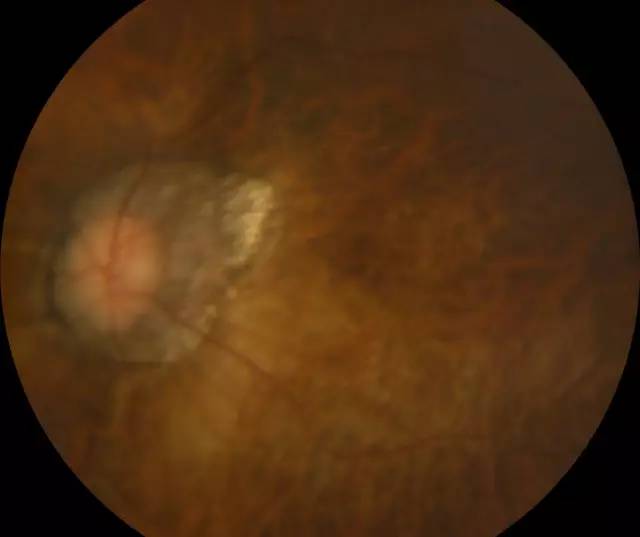

肖先生左眼术前眼底照相图

二天,赶上周末,家人陪着肖先生连忙赶到深圳以诚为本赢在诚信9001进行诊治。经过一系列检查,确诊肖先生为超高度近视裂孔性视网膜脱离,由于黄斑区视网膜全部脱离,必须要尽快做手术。

当日下午,赵铁英院长便为肖先生进行了急诊视网膜脱离手术。因为肖先生是 少数的超高度近视,比正常人的眼球直径扩张很多,眼球壁相当薄,且视网膜脱离颇为严重。赵院长选择何种手术方式都有其困难所在,视网膜薄、球壁也薄,无论是内路手术还是外路手术都非常艰难、各有利弊,所以赵院长在术前选择手术方式的时候,就要争取较大可能尽量避开各种不利因素,取得较大 。